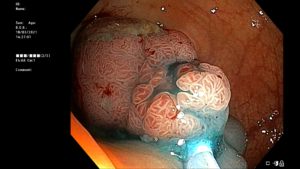

Les anomalies détectées lors d’une coloscopie peuvent être une excroissance de tissus nommés polypes, de diverticules (hernies), la présence de tissus lisses d’aspect anormal ou une inflammation. L’analyse des prélèvements au microscope permettra de poser le diagnostic. La présence d’anomalies n’indique pas nécessairement qu’il s’agisse d’un cancer, la majorité des polypes étant bénins ; néanmoins, leur élimination permet de prévenir l’apparition de la maladie.

Une fois sous anesthésie générale, le coloscope est introduit par l’anus puis progressivement amené jusqu’au côlon. Afin de déplisser les tissus, le côlon est gonflé par de l’air permettant ainsi une bonne visualisation de toutes les parois. Au fur et à mesure de la progression du coloscope, des images sont directement transmises et analysées par le gastroentérologue. Si des anomalies sont détectées, un échantillon de tissu est prélevé pour analyse ultérieure (biopsie). Il est également possible que l’intégralité du tissu anormal soit enlevée (ablation).